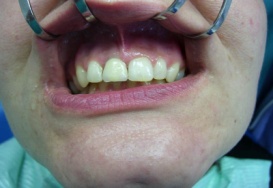

Náhrada jednoho zubu pomocí implantátu je možná také v postranním úseku chrupu. Při ztrátě většího počtu zubů ve frontálním nebo postranním úseku může být mezer uzavřena větším počtem jednotlivých implantátů.

Při ošetření pomocí jednotlivých implantátů zůstávají sousední zuby neporušené – intaktní. Při klasickém ošetření pomocí můstků musejí být tyto zuby obroušeny!